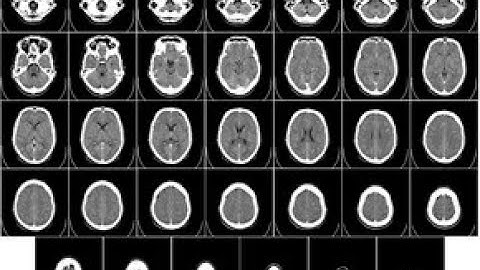

Brain CT scan Filming Protocol on Console of Toshiba 16 Slice in English.